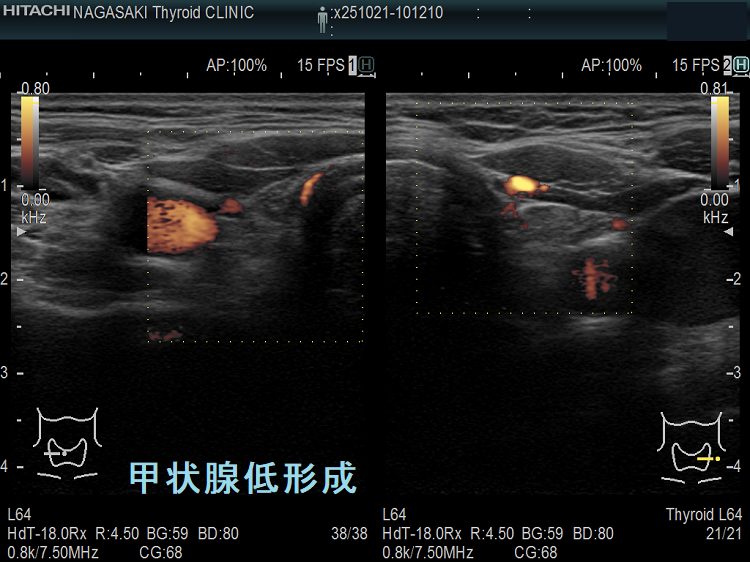

甲状腺低形成 ドプラーモード

甲状腺低形成 超音波(エコー)画像(横断)ドプラーモード;チラーヂンS補充にて甲状腺機能正常の状態だが、内部血流は少ない